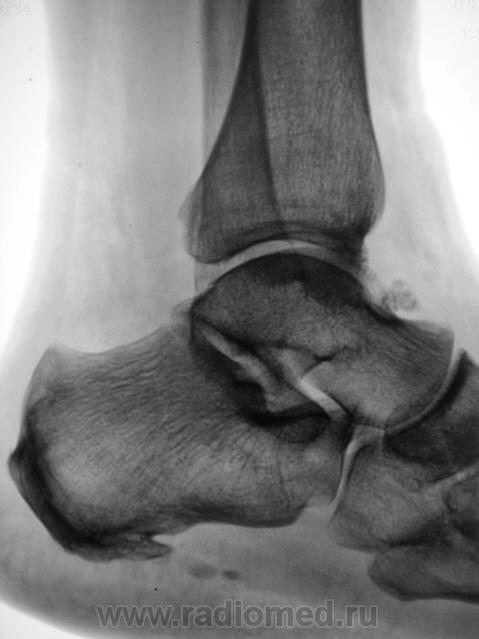

Трах... и вырос "грибок" на таранной...

Грибок этот не "трахогенной" природы. У меня вообще сомнения, что это вырост кости.

Понятно конечно, что "грибок" случайная находка. Но травма была...

Лодыжка срастется, никуда не денется. А вот оссифицирующий апоневрозит и данный то-ли экзостоз, то-ли оссификат капсулы будут периодически доставать и пациента, и врача-куратора.

Больше склоняюсь к хондромному телу, хоть в данном месте не встречал

Грибок этот не "трахогенной" природы. У меня вообще сомнения, что это вырост кости.  +1 !     Больше похоже на обызвествление сосудов . А хондроматоз - не подходит по локализации , хотя сама тень похожа внешне .